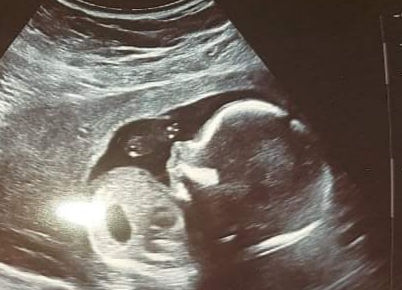

Určitě tě nemine 3D ultrazvuk.

Mě to spíš přijde jako kus ruky a prstů ;)